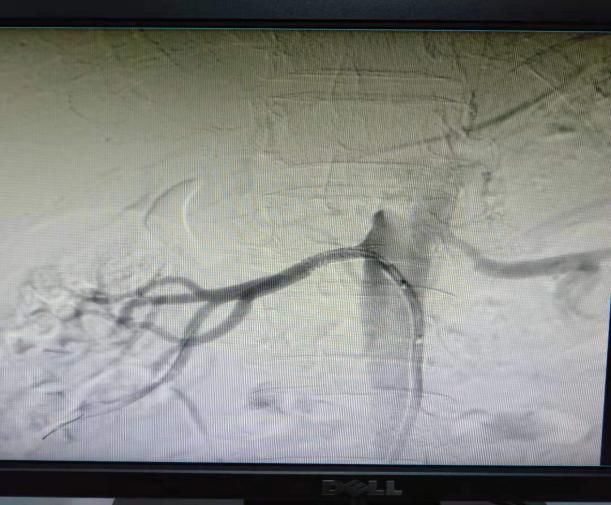

(1)2018年12月12日开展第一例肾动脉支架植入术。

患者:赵某 男性 49岁 岳村镇

图片

术前

术后